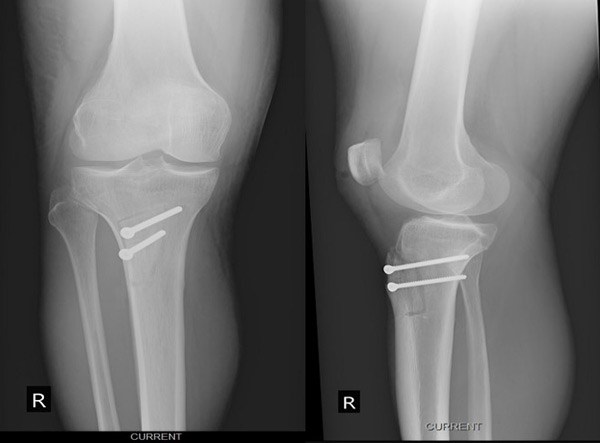

Management of chondral ‘kissing’ lesion of patella and trochlea: Post-operative X-Rays

Post-operative X-Rays